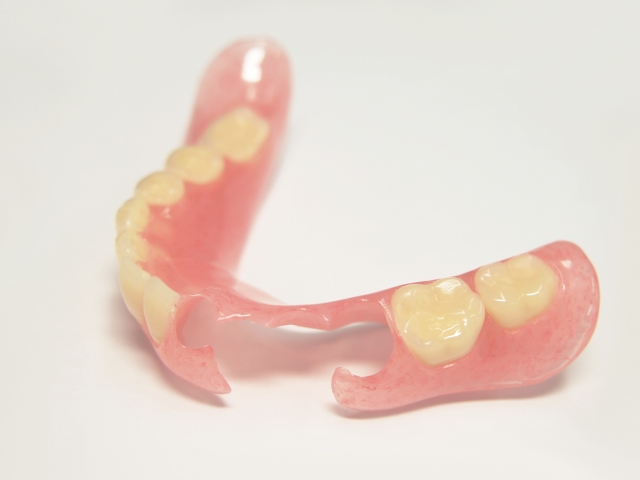

75歳男性

「ブリッジが外れてしまい、全く噛めなくなった」とのことでご相談いただいた患者さまです。上顎には着脱式のテレスコープ義歯、下顎には金属バネのあるクラスプ義歯を採用しました。ご高齢でインプラントには抵抗があるとのことでしたので、外科処置を伴わない選択肢をご提案しています。

テレスコープ義歯は一般的な入れ歯と比べてフィット感が高く、ズレやこすれによる痛みが出にくいのが特徴です。金具が見えない設計のため、見た目にも自然で、入れ歯を装着していることがほとんどわからない仕上がりとなりました。

| 主訴 | ブリッジが外れてしまい、全く噛めなくなった。 |

| 治療内容 | 上顎テレスコープ義歯(着脱式)下顎クラスプ(金具タイプ)義歯 |

| 治療期間 | 2年間 |

| 治療費 | 約3,000,000円(上下合計) |

| リスク・副作用 | ※予後を完全に保証する治療ではありません。※自由診療での治療です。※精密な装置であるため装置が落としたときに破損する時があります。 |